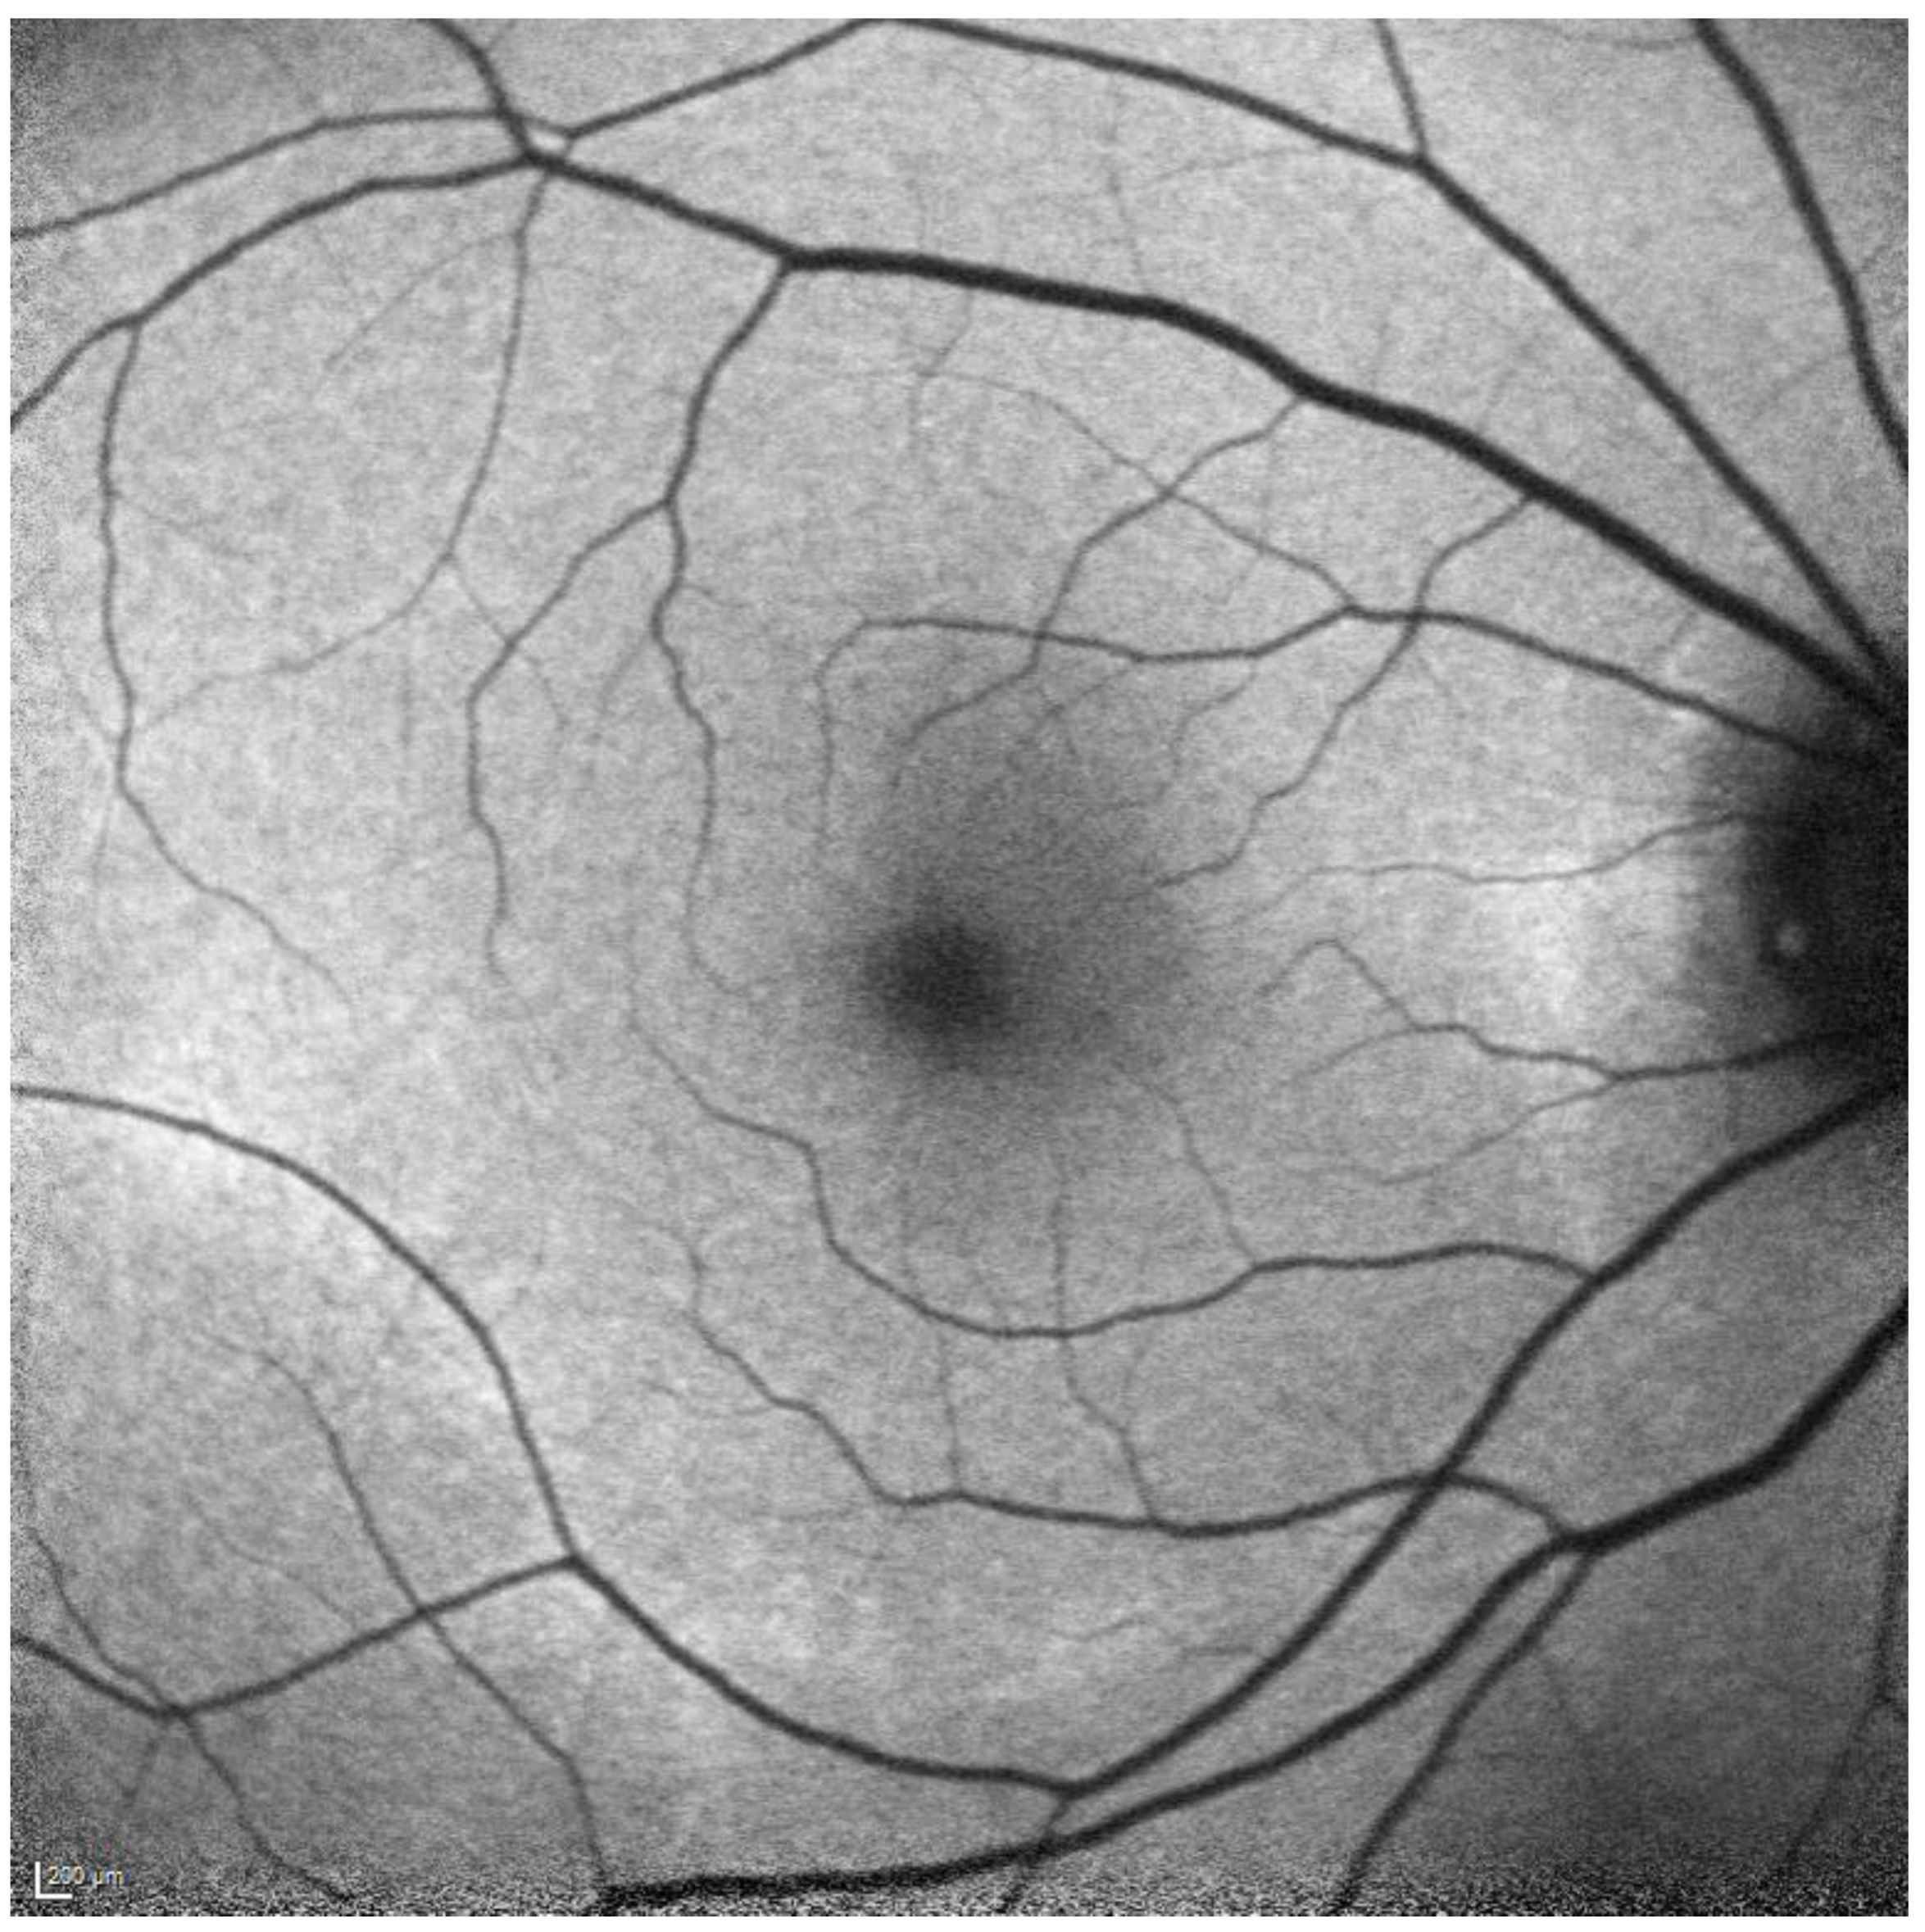

2.2. Fundus Autofluorescence

2.3. Comparison of OCT and FAF

3.2.1. Quantitative Autofluorescence

3.2.2. Near-Infrared Autofluorescence